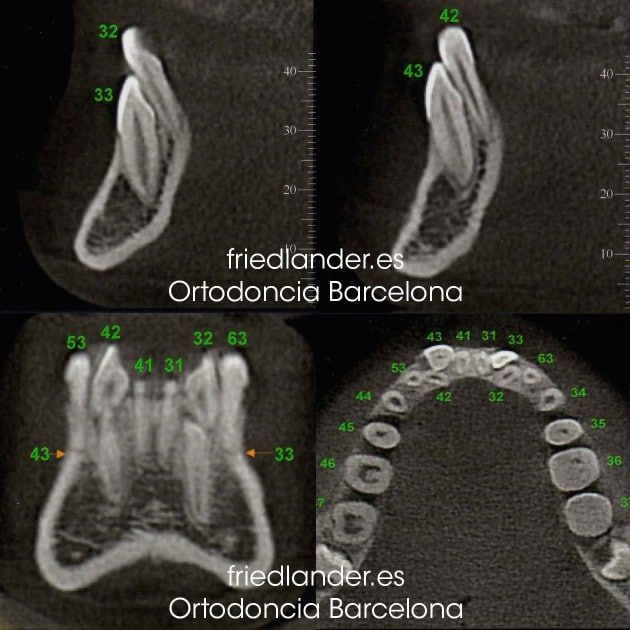

Para conocer la posición exacta de los caninos con respecto a los dientes vecinos pedimos una tomografía computerizada de haz de cono (CBCT es una tomografía computerizada dental)

Los caninos inferiores están incluidos y en transposición con los incisivos laterales (cambio de lugar); una posición muy desfavorable para colocarlos en su sitio en la arcada dental. Podemos plantear el caso de tres maneras con respecto a los caninos inferiores: